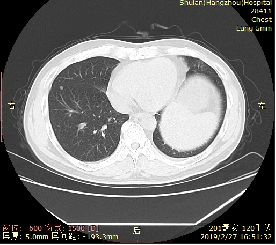

2018-6-21肺部CT提示多发转移。

2018-6-21肺部CT

2018-8-3肺部CT

2018-9-22肺部CT

2018-12-7肺部CT

瑞戈非尼治疗前

瑞戈非尼治疗1月后

瑞戈非尼治疗2个半月

瑞戈非尼治疗5个月

治疗15个月后